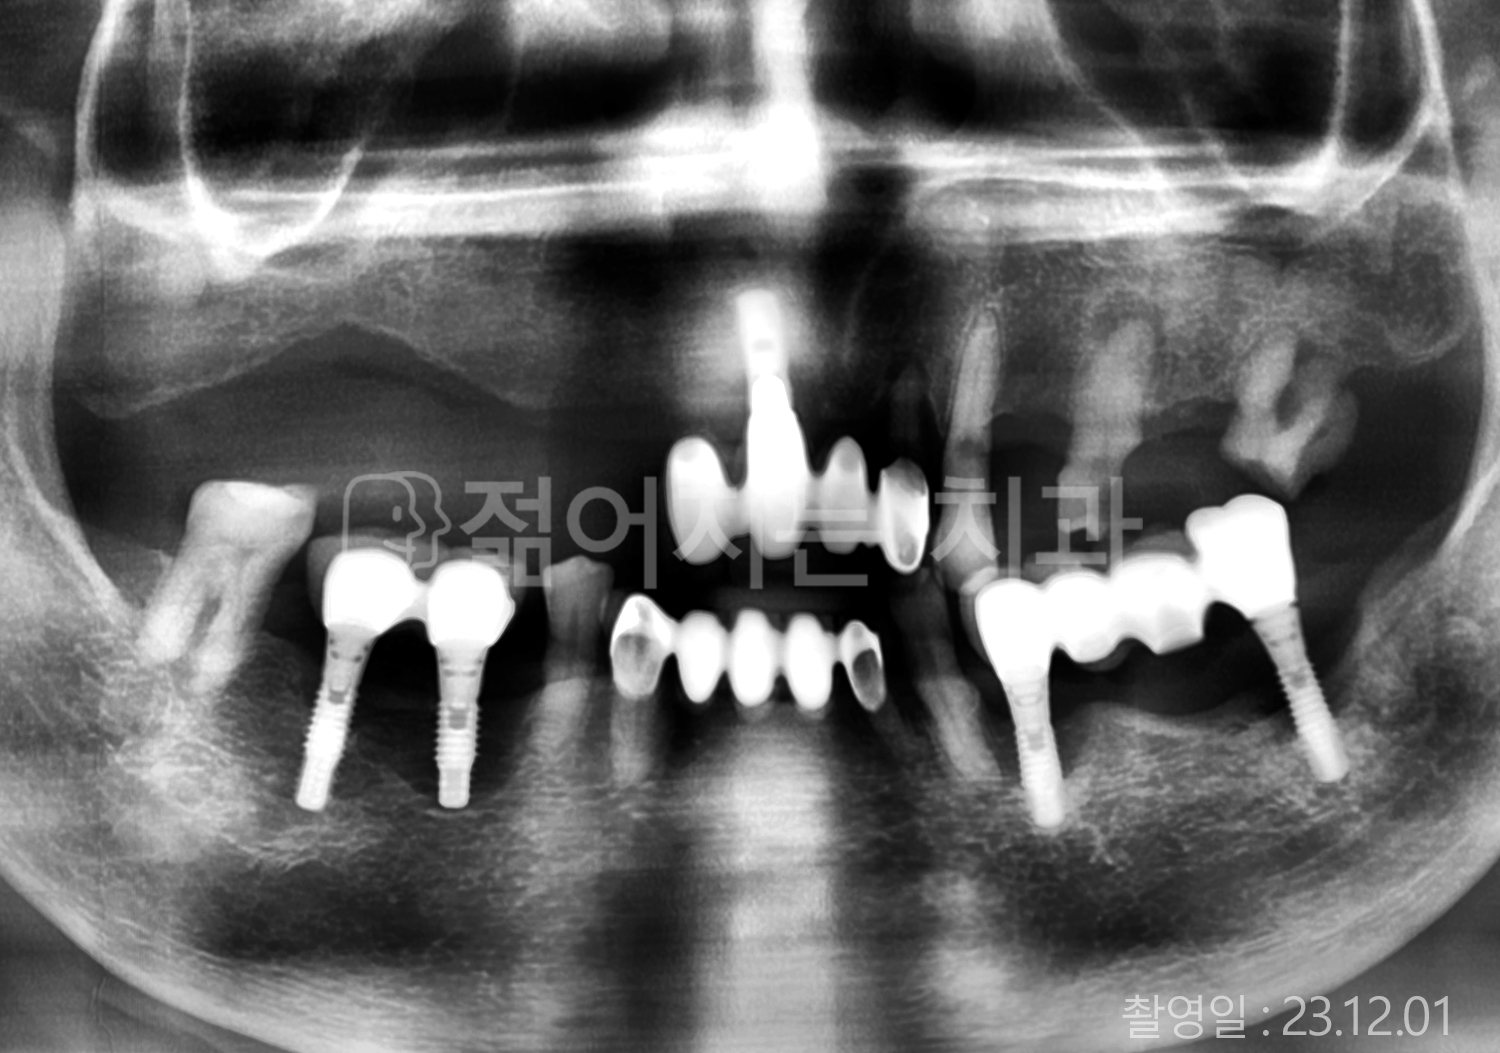

• 70대 고혈압, 고지혈증 전체치아 10개 이상 임플란트

• 60대 당뇨, 간염 전체치아 10개 이상 임플란트

• 80대 골다골증 전체치아 6개 이상 임플란트

• 70대 고혈압, 당뇨 전체치아 10개 이상 임플란트

• 60대 간 질환 전체치아 10개 이상 임플란트

• 60대 전체치아 10개 이상 임플란트

• 70대 전체치아 10개 이상 임플란트

• 50대 전체치아 10개 이상 임플란트